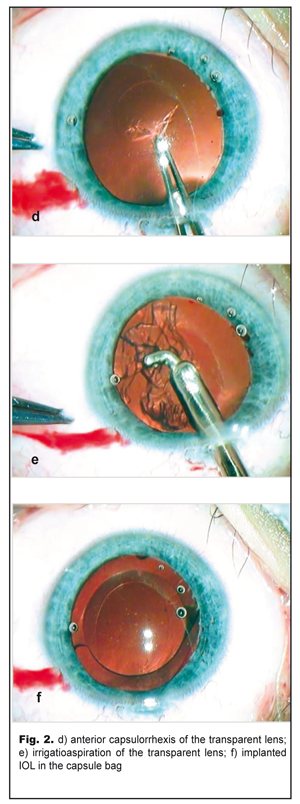

On completion of d=5.5 capsulorrhexis (Fig. 2d) and phacoaspiration of the clear lens (Fig. 2e), an IOL, SN60WF 16.0 D, was implanted into the capsule bag using a cartridge (Fig. 2f). The pupil narrowed symmetrically in response to myotic administration into the anterior chamber; viscoelastic was aspirated and the incision was sutured. The postoperative period was without abnormalities. Results and Discussion The left eye was calm with a clear brilliant cornea, an average depth anterior chamber, and transparent aqueous humor. The round pupil, in the center, constricted well (Fig. 3a) and evenly dilated by mydriatics to 6.0 mm; herewith, bases of the dissected PPM strands could be seen along the inner edge of the pupil (Fig. 3b). The Acrysof IOL was correctly placed in the capsule bag; behind the IOL there was a transparent anterior capsule. The eye fundus reflex was even and pink with details in norm. IOP was normal.